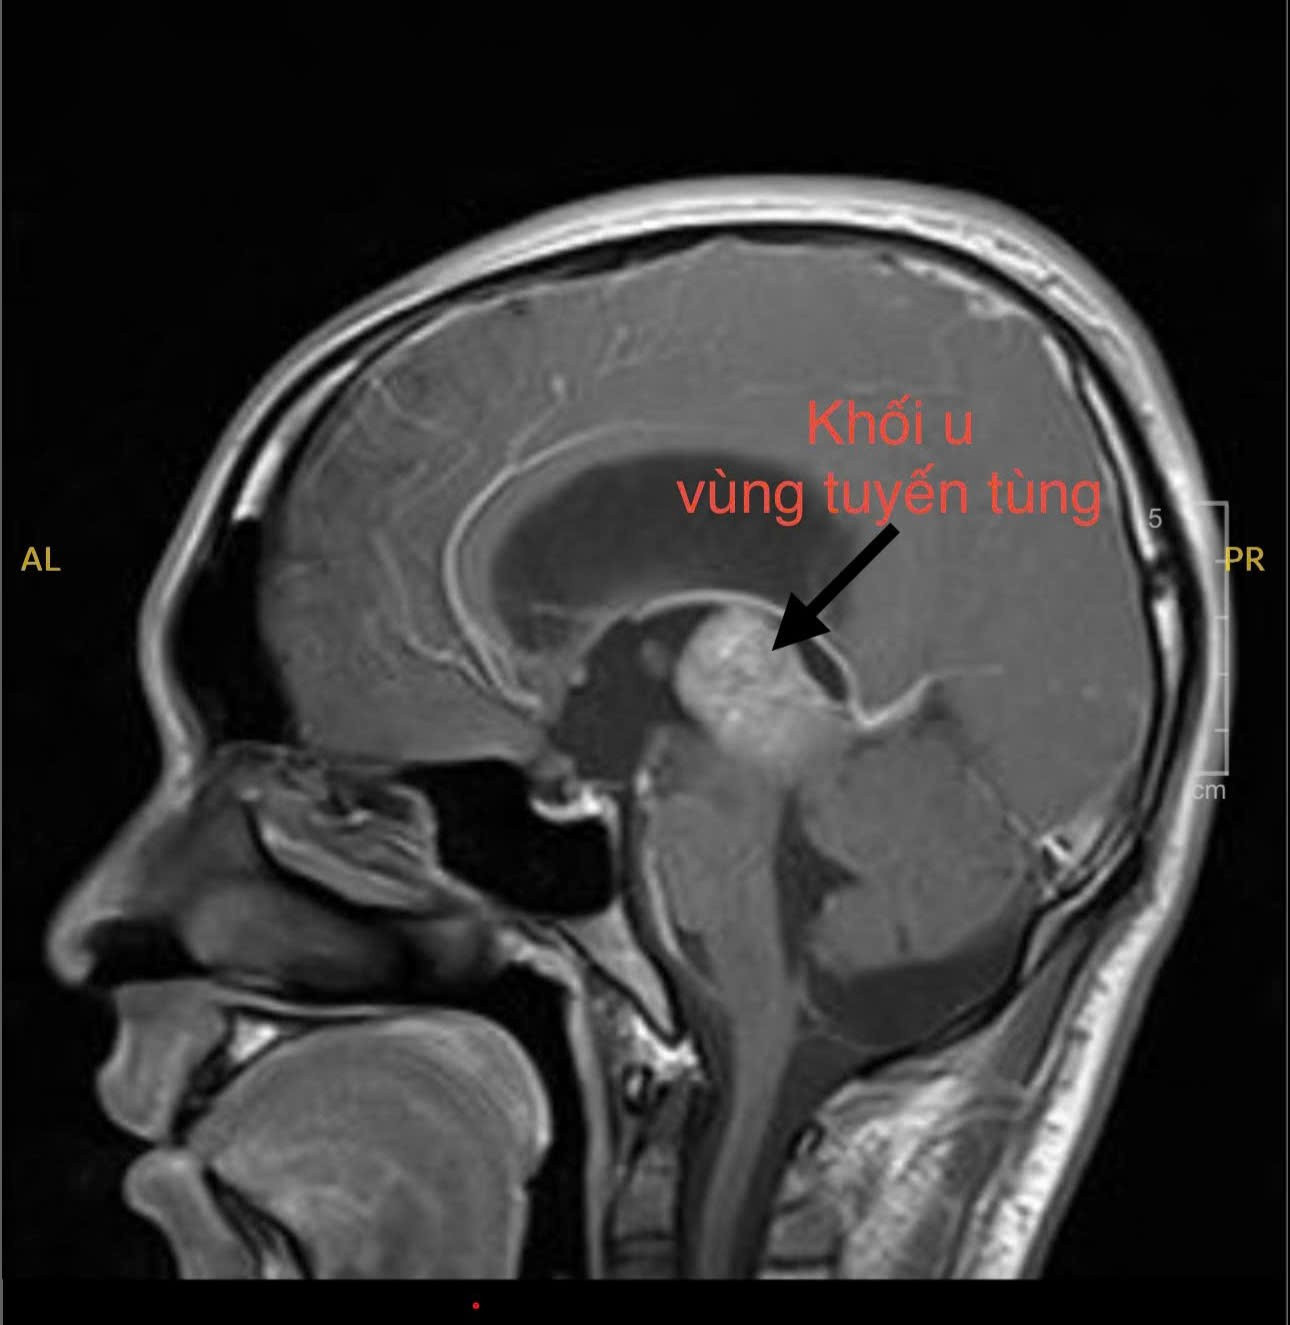

Nhận thấy tình trạng bất thường, người mẹ đã đưa con đến cơ sở y tế địa phương thăm khám. Tại đây, bác sĩ chỉ định chụp MRI não. Hình ảnh ghi nhận một khối u vùng tuyến tùng – vị trí nằm sâu giữa não, có thể gây chèn ép đường lưu thông dịch não tủy. Theo bác sĩ, đây chính là nguyên nhân khiến áp lực nội sọ của H. tăng cao, dẫn tới đau đầu dữ dội và các rối loạn kèm theo.

Theo BS Huy, khối u vùng tuyến tùng là bệnh lý hiếm gặp, chỉ chiếm khoảng 1% u não ở người lớn và 3 – 11% ở trẻ em, tập trung nhiều ở nhóm từ 10 đến 20 tuổi. Khối u nằm tại tuyến tùng, đây là tuyến nội tiết nhỏ nằm sâu trong não, khi phát triển có thể chèn ép cống não và não thất III, gây não úng thủy, một biến chứng rất nguy hiểm.